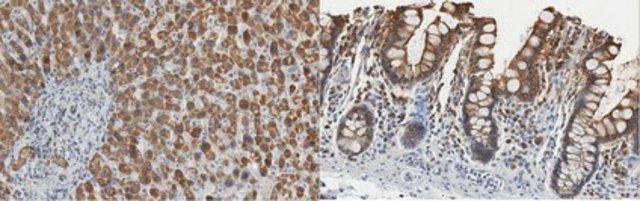

Immunohistochemistry Analysis: A 1:1,000 dilution from a representative lot detected NRF2 in human liver, human small intestine, human tonsil, and human pancreas.

Clone 6H11.1 detects NRF2 in HepG2 cells. It targets an epitope within 15 amino acids in the C-terminal region.